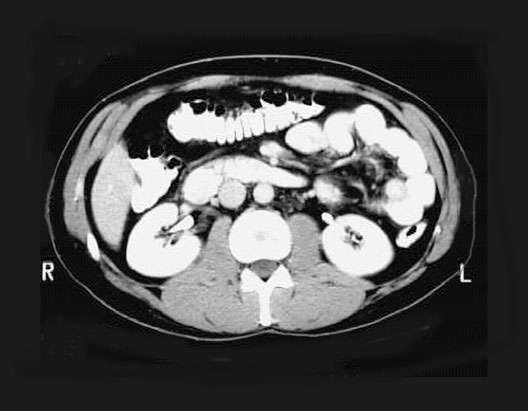

Abdominal CT

1. Duodenum - Junction of 2nd and 3rd Parts

2. Inferior Vena Cava

3. Transverse Colon

4. Duodenum - 3rd part

5. Abdominal Aorta

6. Left Kidney

7. Psoas Muscle

8. Right Kidney